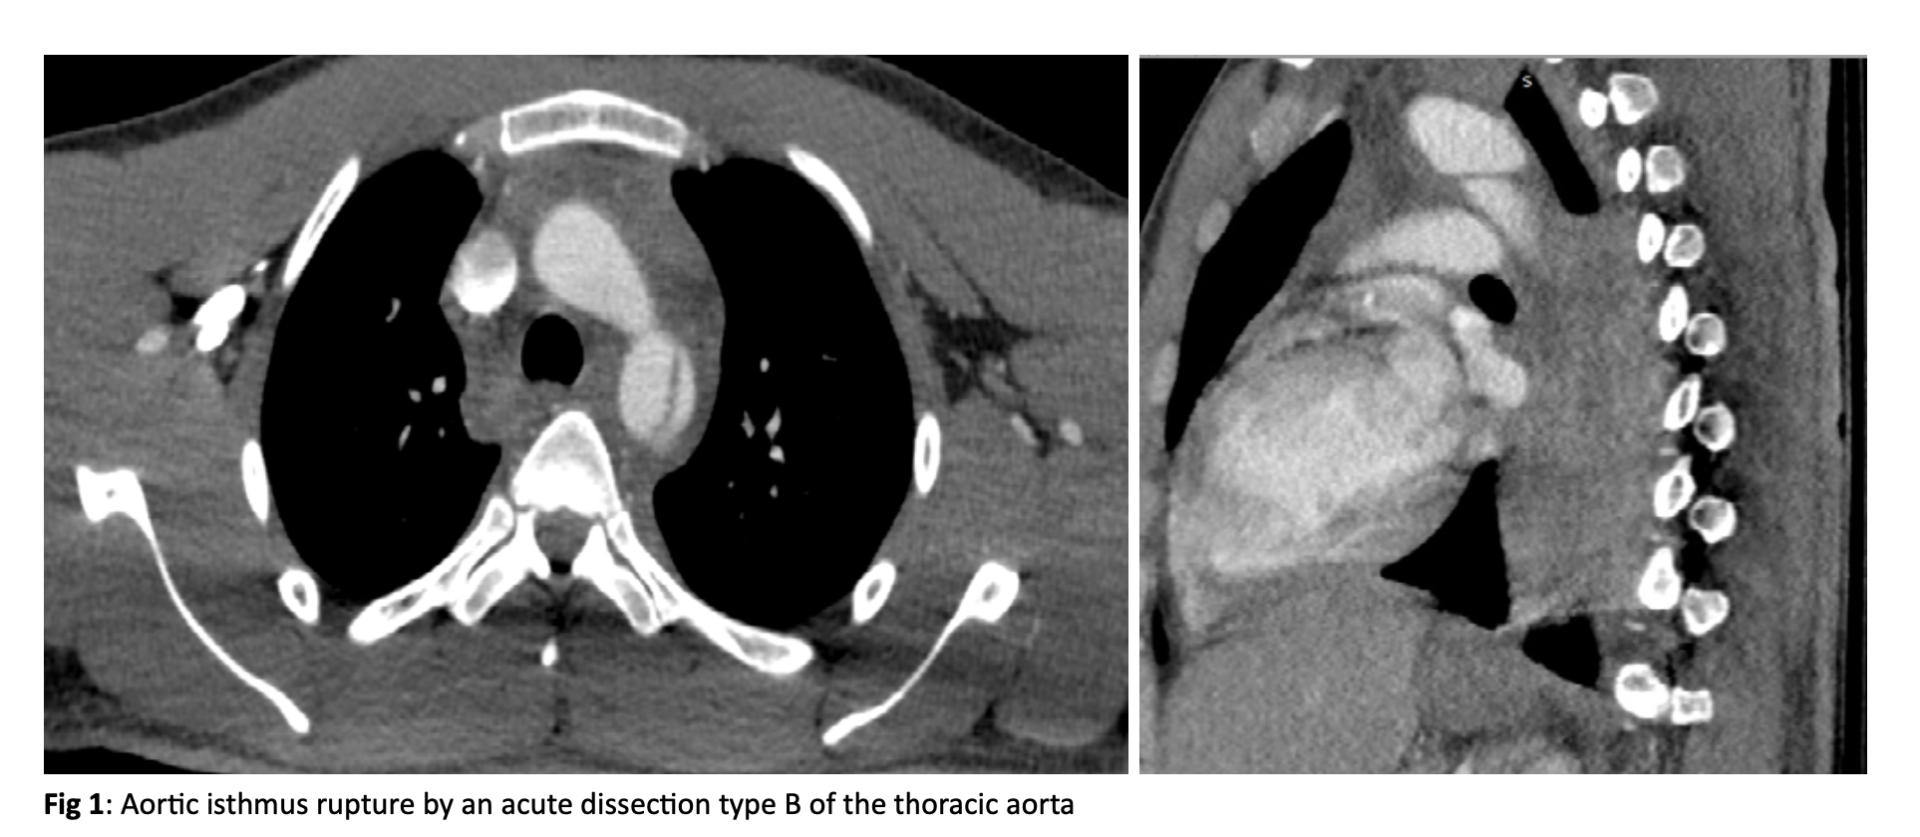

A 21-year-old male patient, with unknown personal or family medical history, was transferred unconscious to our emergency department because of a mentioned traffic accident. He was intubated urgently in the emergency department. In full body computed tomography angiography (CTA) was observed an aortic isthmus rupture by an acute dissection type B of the thoracic aorta (Figure 1). The dissection was originated distal to the LSA and extended proximal to the celiac artery (C.A.). Moreover, it was observed a mandibular fracture.